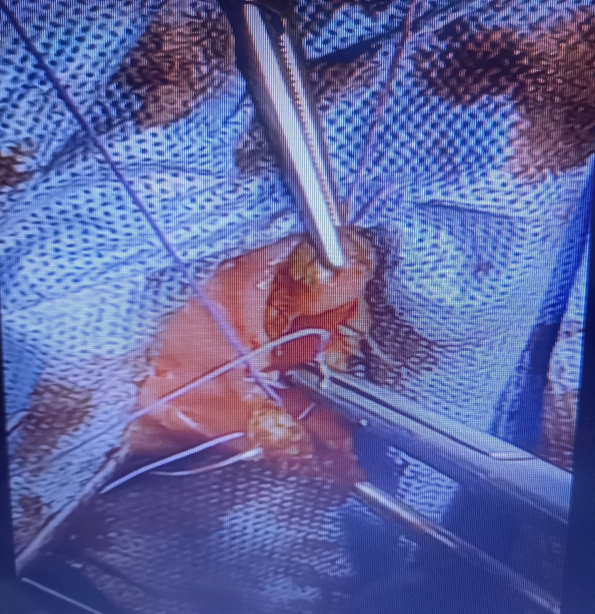

The patient underwent a hymenotomy and surgical drainage of the hematocolpos. A circular (annular) incision at the center of the bulging hymen was performed by electrocautery, followed by drainage of approximately 2500ml of thick brownish menstrual blood and diligent irrigation of the vagina (Figure 4). Care was taken to spare hymenal tissue circumferentially from the base in order to preserve virginity. A normal cervix was visualized and inspected. The vaginal entrance was surgically restored as follows: The edges of the vaginal margins were everted by suturing the inner vaginal mucosa to the exterior vestibular mucosa with absorbable No2 sutures, firstly by performing single interrupted sutures which were then followed by a purse-string suture (Figure 5). Vaginal swabs were collected and the results of the cultures were negative for infection. A penrose tube was placed at the introitus to ensure unimpeded continuous drainage and was removed on the second postoperative day. Broad-spectrum antibiotics were administered for post-operative chemoprophylaxis. The postoperative course was uncomplicated and the patient was discharged on the fourth postoperative day. Her wound had completely healed by the time she had her three-month post-op follow-up appointment (Figure 6). To this day, she has been experiencing normal painless menses.

Figure 4 Surgical drainage of hematocolpos through an annular incision.